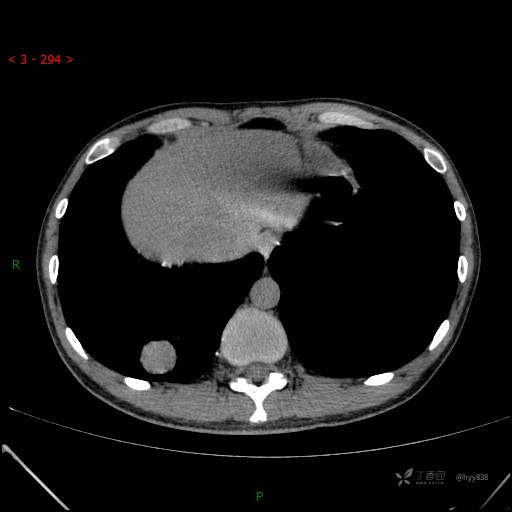

增强动脉期